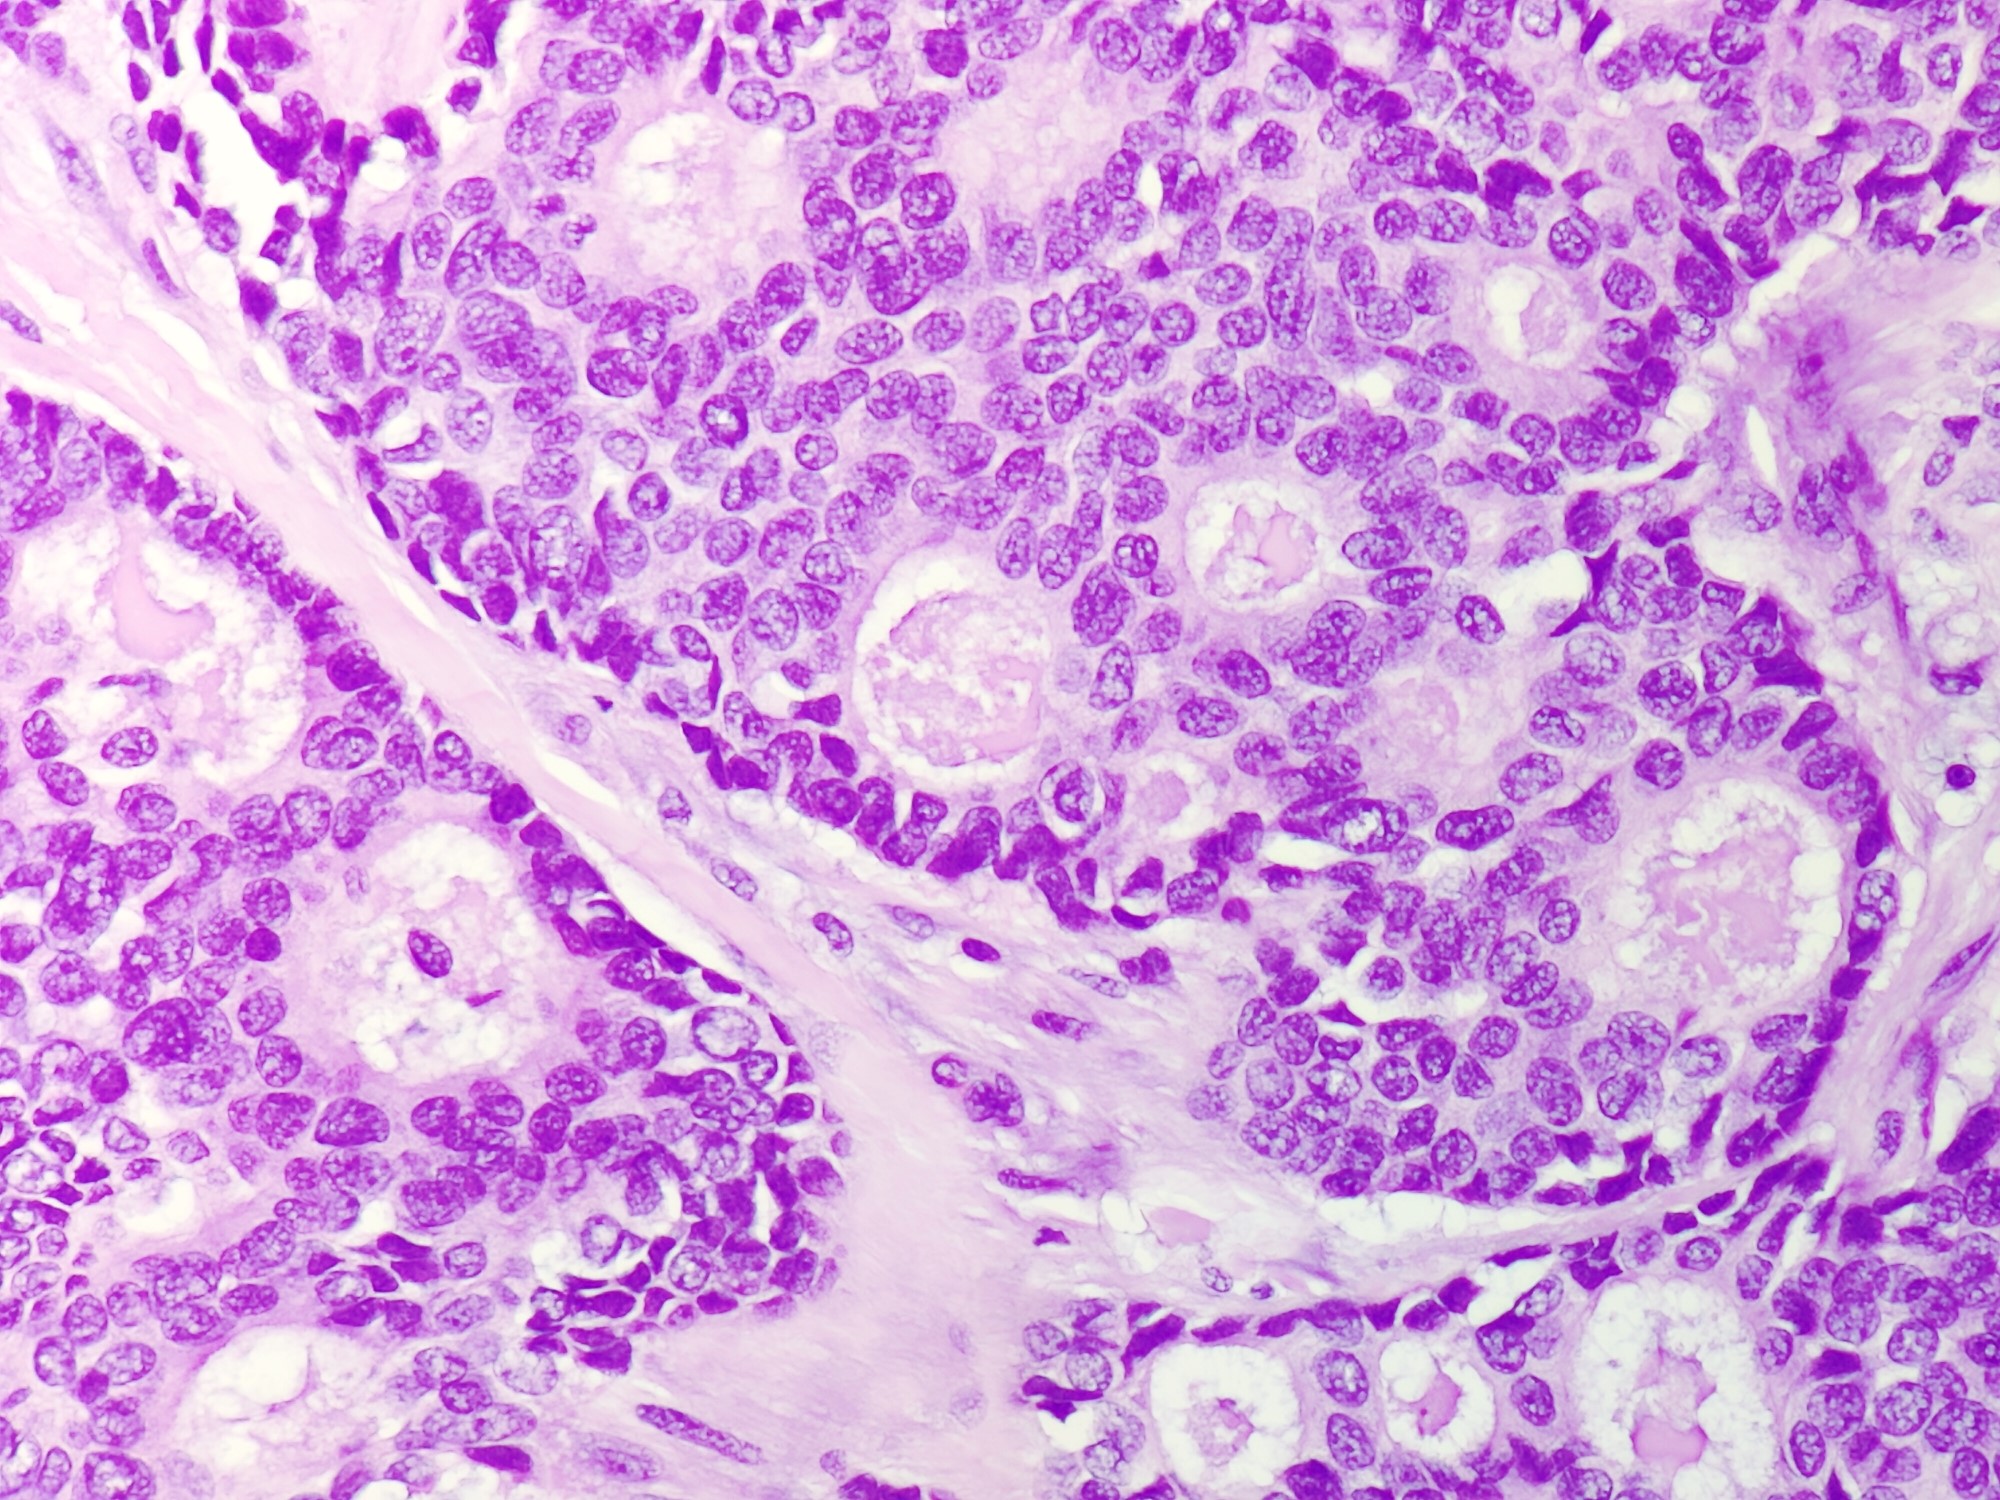

Microscopic (histologic) description

- Irregular cribriform growth pattern > 90% of cells

- Nuclear grade I pure ICC: > 90% cribriform pattern

- Mixed: 10 - 90% other morphological type, other than cribriform carcinoma

- Low grade: Nottingham grade 1 tumors

- Invasive islands or nests of malignant cells with round or angulated contours and well defined cribriform spaces formed by arches of epithelial cells; this gives a sieve-like appearance

- Tumor cells: small, mild / moderate pleomorphism, no nuclear atypia

- No / sparse mitotic activity

- Desmoplastic stroma

- Mucin positive secretion, microcalcifications in lumen

- Osteoclastic giant cells may be seen

- Myoepithelial cells absent

- Associated with cribriform ductal carcinoma in situ (DCIS)

Microscopic (histologic) images

Contributed by Sunitha Shankaralingappa, M.B.B.S, M.D., D.M.